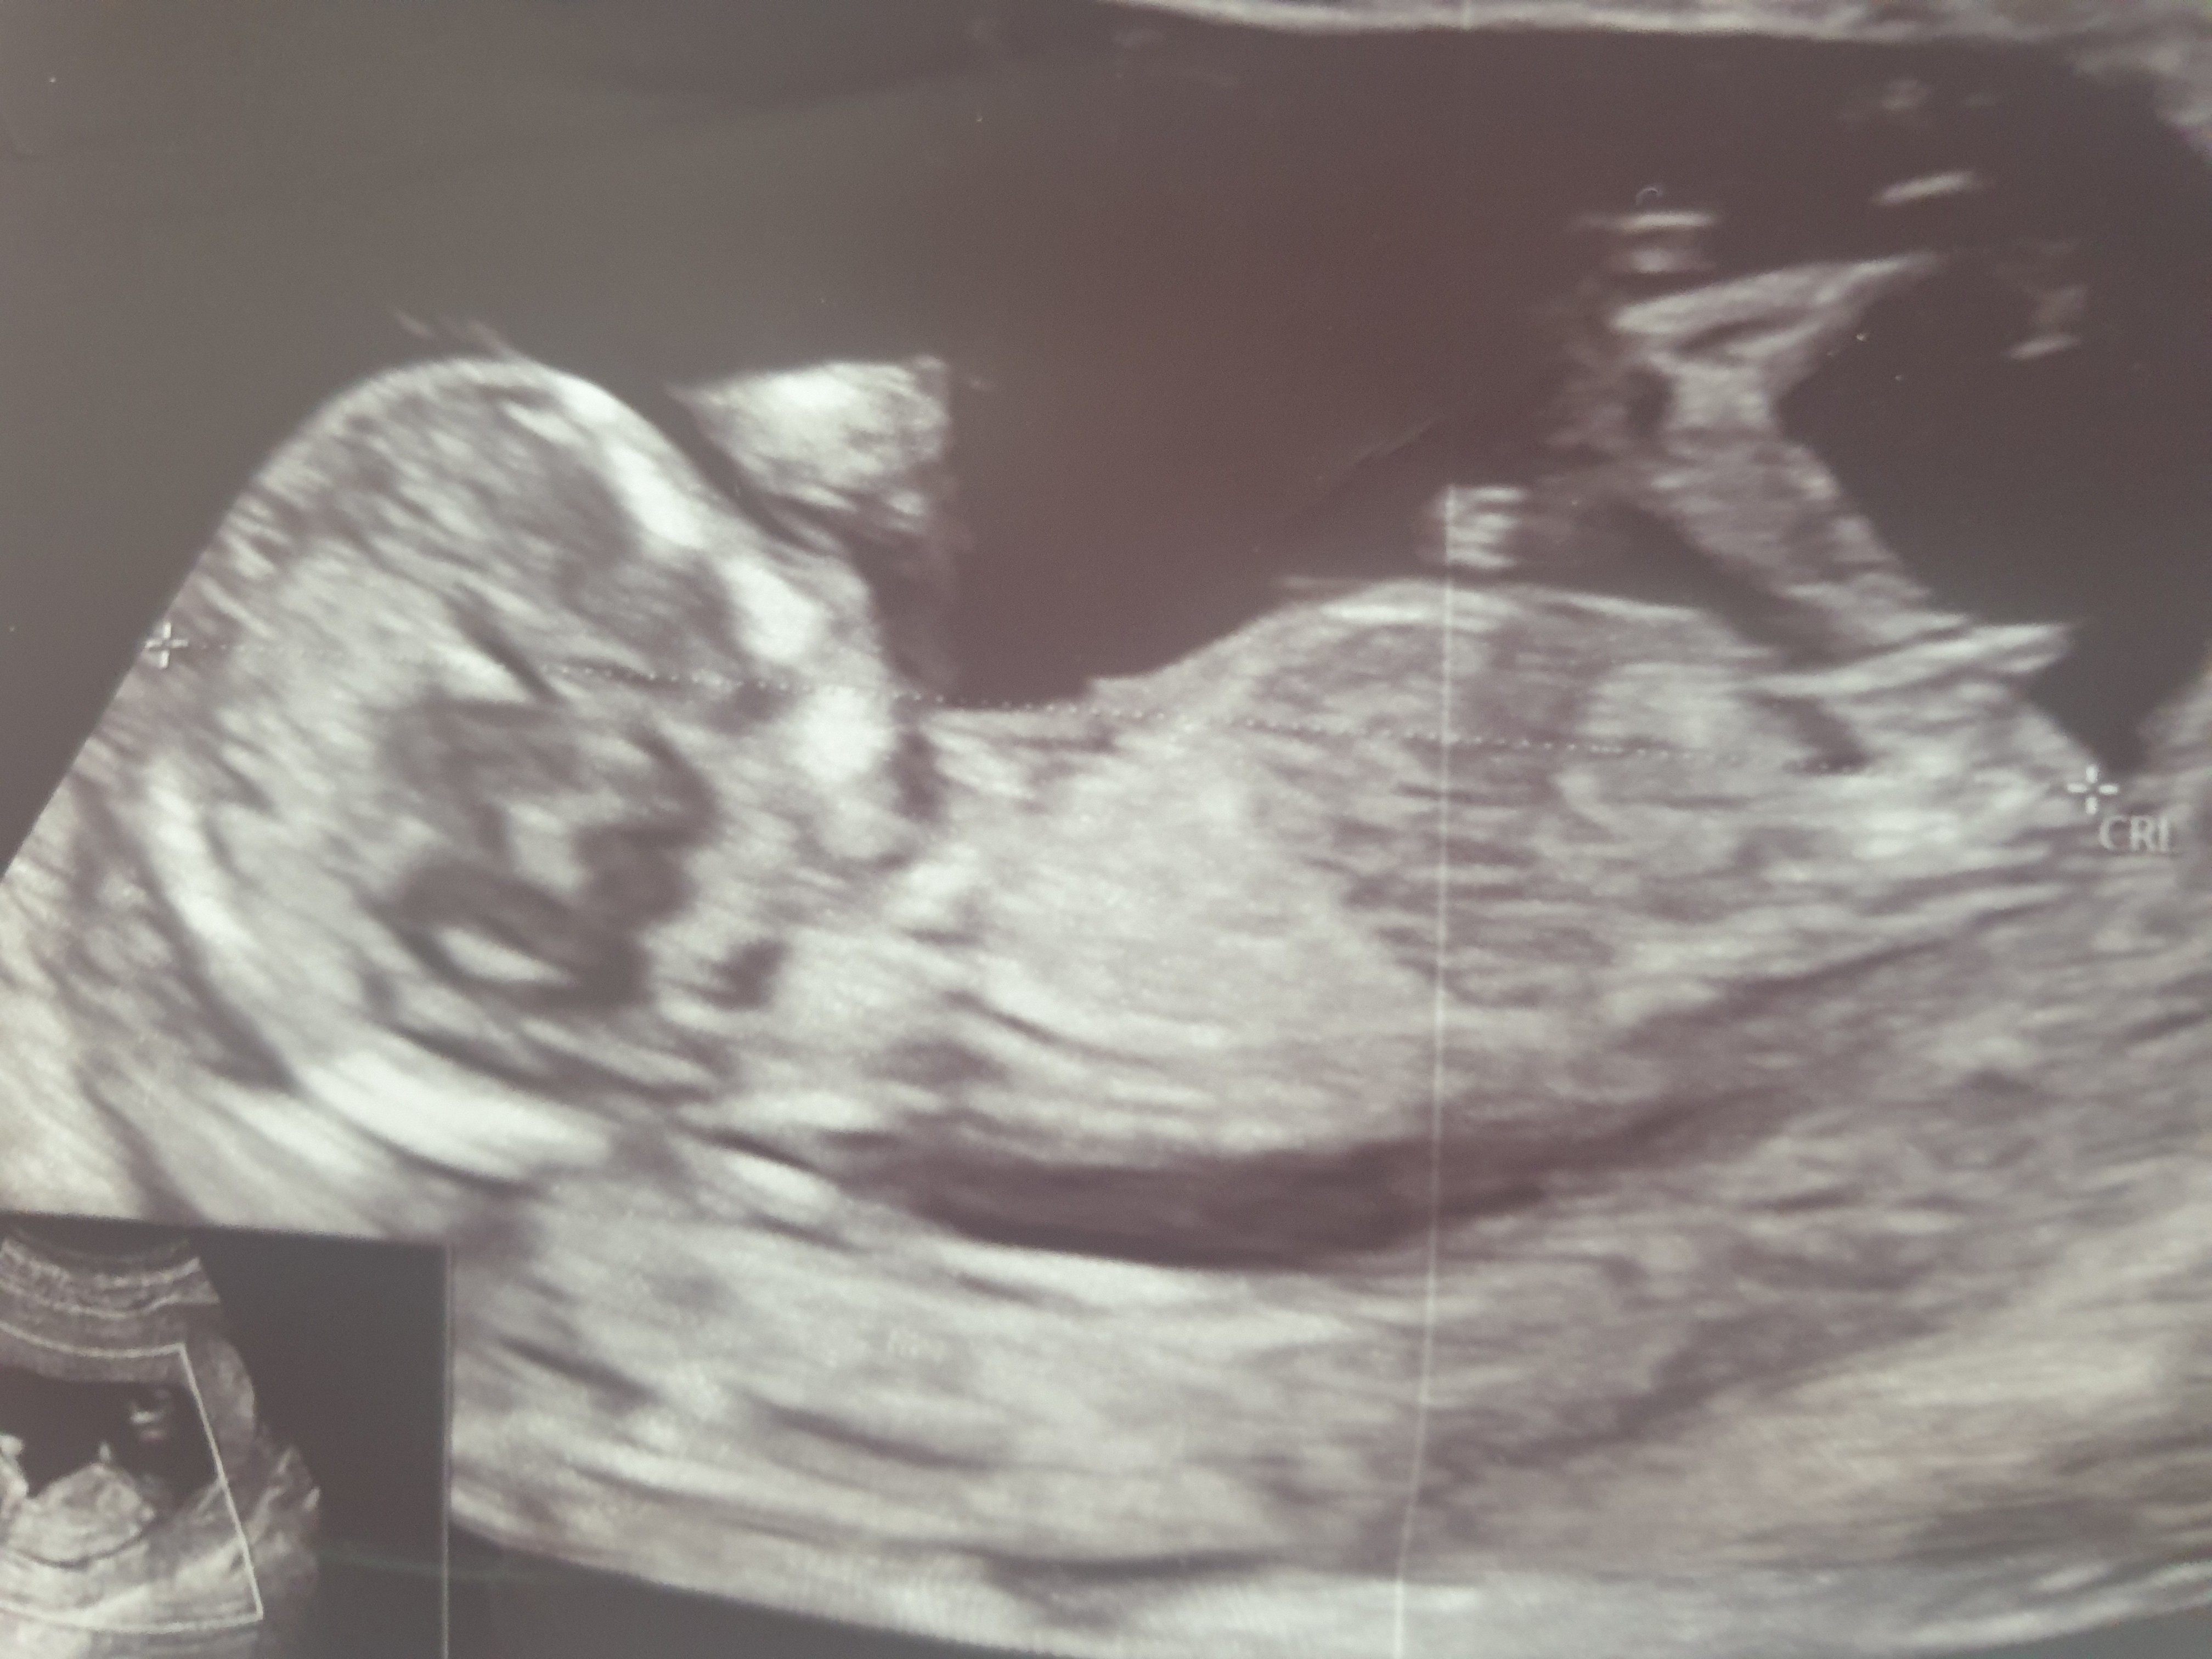

Dziewczyny, 12+4. zdjęcie z pierwszego badania prenatalnego, doktor "przewidział" płeć, ale nie ukrywam, że mam lekką nadzieję, że może jeszcze coś się zmieni :D Jaka jest Wasza opinia? Dziewczynka czy chłopiec ? Czy zdążyło się Wam, że werdykt z 13go tygodnia się zmienił ?

• 20240615_113518.jpg

20240615_113518.jpg

1,4 MB · Wyświetleń: 1 296